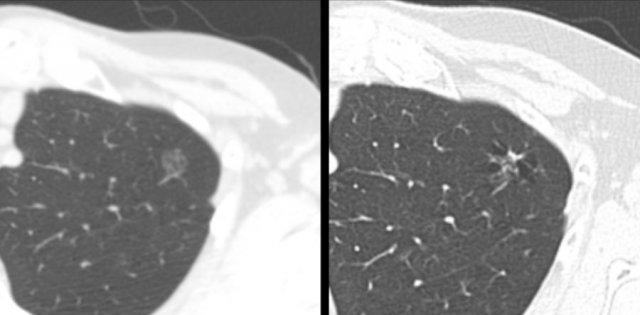

Bệnh nhân ung thư biểu mô tuyến T1c ở thùy trên phổi trái (hình bên trái). Tổn thương dạng nang đồng thời đang phát triển ở thùy dưới phổi phải (hình bên phải) được xác định là ung thư biểu mô tuyến nguyên phát thứ hai không liên quan trên kết quả mô bệnh học. Trong thực hành lâm sàng hàng ngày

Thứ nhất, đã được ghi nhận rằng ung thư phổi dạng nang thường đại diện cho một khối ác tính nguyên phát thứ hai, có thể xuất hiện không đồng thời (metachronous) hoặc đồng thời (synchronous) với ung thư phổi đầu tiên (hình minh họa).

Các hình ảnh này thuộc về một bệnh nhân có ung thư biểu mô tế bào vảy dạng nang ở thùy dưới phổi trái (hình bên trái), người đã xuất hiện tổn thương dạng nang ở thùy dưới phổi phải (hình bên phải) và hạch bạch huyết to vùng dưới carina sau 3 năm theo dõi.

Mặc dù ban đầu được xem xét là bệnh di căn đối bên, phân tích mô học được khuyến nghị đã cho thấy đây là ung thư biểu mô tế bào vảy nguyên phát thứ hai không liên quan trên kết quả mô bệnh học.